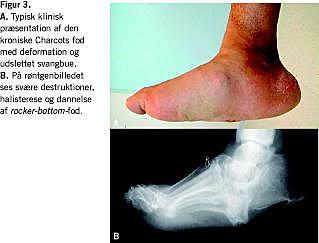

Tilstanden viser sig ved ensidig hævelse, varme og evt. rødme (Figur 2). Patienterne anfører ofte, at de har ukarakteristiske symptomer i form af uro, murren og fornemmelse af instabilitet, men de har i reglen ingen smerter. CA kan opstå symptomfattigt, blot med hævelse og øget hudtemperatur, men diagnosen bør alligevel haves in mente, og foden bør straks aflastes (se nedenfor). En del af patienterne har et mindre traume. Et næsten gennemgående karakteristikum er et forløb på 1-3 måneder mellem symptomstart og diagnose. Dette indebærer ofte udvikling af deformitet, inden behandlingen sættes ind. Deformitet er oftest karakteriseret ved sammenfald af fodbuen, i værste fald i form af en såkaldt gængefod (rocker-bottom) -deformitet med plantar konveksitet (Figur 3). På grund af den ændrede fodarkitektur vil disse patienter have en abnorm trykfordeling plantart. Dette kombineret med neuropatien medfører callusdannelse og en øget forekomst af fodsår [5]. Risikoen for fodsår er øget med en faktor 4-5, svarende til en incidens på knap 20% [16].